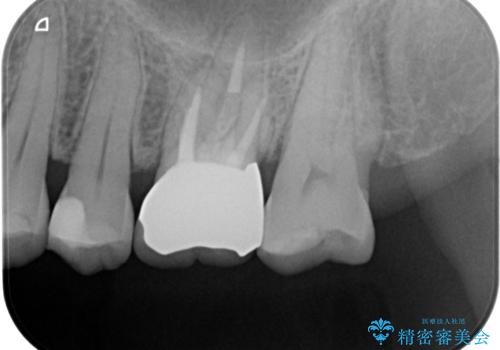

虫歯を取りきった後セラミッククラウンでの修復処置を行います。

- 左上6/仮歯+ジルコニアクラウン:11,000円+110,000円 (根管治療:保険)費用は治療当時の料金となります

今回は過去に治療された部分をすべてやり直しました。

再治療にならないような精密な治療が重要です。